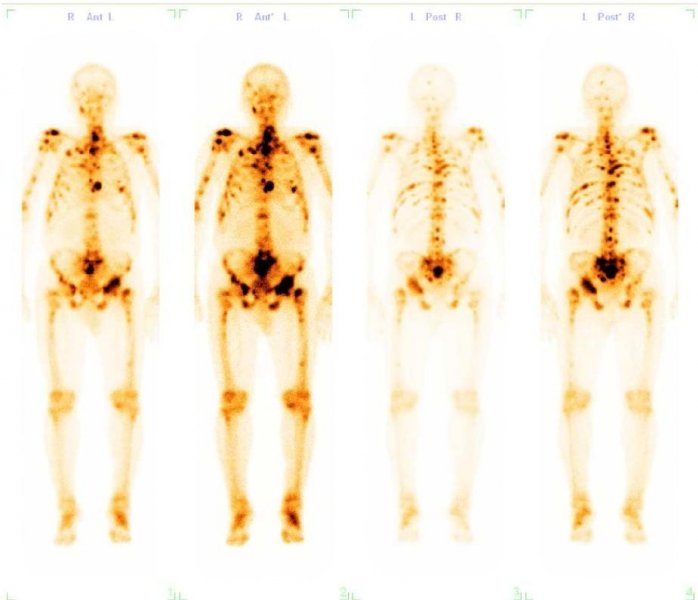

Przykładowe obrazy scyntygraficzne uzyskiwane w naszym Zakładzie Medycyny Nuklearnej: